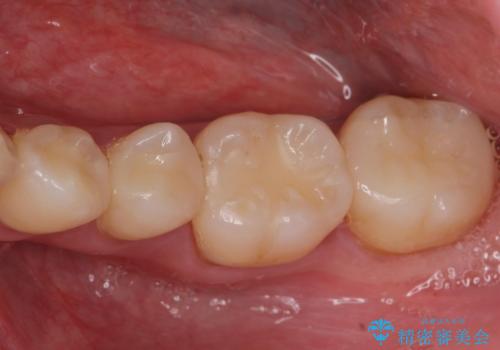

e-maxインレーによる治療

- 定期検診で来院してレントゲンを撮ったところ

歯と歯の間にう蝕ができていました。

拡大鏡下でう蝕を全て除去してe-maxインレーにて治療を行いました。